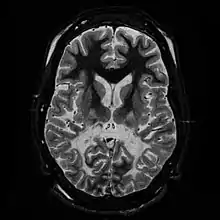

White matter, with reduced volume and increased signal intensity. The anterior white matter is spared. Features are consistent with X-linked adrenoleukodystrophy.

The Loes score is a rating of the severity of abnormalities in the brain found on MRI. It ranges from 0 to 34, based on a point system derived from the location and extent of disease and the presence of atrophy in the brain, either localized to specific points or generally throughout the brain. A Loes score of 0.5 or less is classified as normal, while a Loes score of 14 or greater is considered severe. It was developed by neuroradiologist Daniel J. Loes MD and is an important tool in assessing disease progression and the effectiveness of therapy.[13]